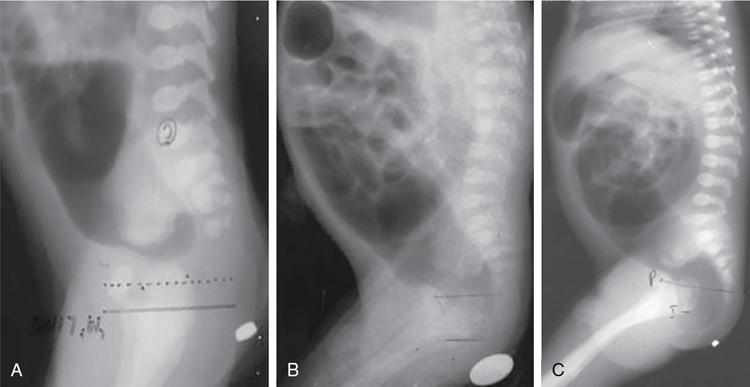

Arun Gupta, Manisha Jana, Devasenathipathy Kandasamy Anorectal malformations (ARM) are uncommon congenital malformations. They can either be found as an isolated anomaly or in association with other congenital malformations. The age of presentation and clinical presentation can have wide variation. In order to understand the complex anatomic details of the ARM, it is imperative to know the embryology and development of the normal anal canal. In the early embryonic life (4th–5th week), the primitive hindgut and the allantois communicate with each other at the cloaca. The membrane covering the cloaca at the caudal end is called cloacal membrane. During the 6th week of gestation, a sheet of mesenchyme (urorectal septum) grows between the allantois and hindgut. Eventually, lateral and midline folds develop in the cloaca, thereby dividing the common cavity into two parts: anteriorly urogenital sinus and posteriorly anorectum. Gradually, the embryo starts to lengthen and curve inwards. As a result, the distance between cloacal membrane and the tip of urorectal septum decreases and eventually, they meet each other. Consequently, the urogenital sinus and anorectum get completely separated (Fig. 7.6.1). In a later stage of gestation (7th–8th week), the anal canal gets secondarily occluded by epithelial plugs, which again gets recanalized to form the lower anal canal. Henceforth, it can be understood that any aberrations in the normal development at an earlier stage of gestation would result in a more severe degree and higher level of communication between urogenital system and anorectum. Any insult at a later stage of development will result in a low ARM, which will mostly have an abnormal anal opening in a normal position and no urogenital communication with the hindgut. Over the years, many classification systems for ARM have been introduced. Three major classifications are: Anorectal agenesis without fistula Anorectal agenesis with Rectal atresia Anorectal agenesis without fistula Anorectal agenesis with Rectal atresia H or N type fistula* Anal agenesis without fistula Anal agenesis with rectobulbar urethral fistula Anorectal stenosis Anal agenesis without fistula Anal agenesis with low rectovaginal fistula Anal agenesis with rectovestibular fistula Anorectal stenosis *Not described in original classification. #Site of anal opening is usually low but variable (1 and 2: at normal anal site; 3 and 4: at perineal site; 5–7: at vulvar location). Anorectal agenesis without fistula Anorectal agenesis with rectoprostatic urethral fistula Rectal atresia Anorectal agenesis without fistula Anorectal agenesis with rectovaginal urethral fistula Rectal atresia Anal agenesis without fistula Rectobulbar urethral fistula Anal agenesis without fistula Rectovaginal fistula Rectovestibular fistula Anal stenosis Anocutaneous fistula Anal stenosis Anocutaneous fistula Anovestibular fistula Rare Rare Anal or anorectal agenesis without fistula Rectal atresia Anal or anorectal agenesis Anal or anorectal agenesis without fistula Rectal atresia Cloacal anomalies Anal stenosis Imperforate anus without fistula Anal agenesis with rectoperineal fistula Anal stenosis Imperforate anus without fistula Anal agenesis with rectoperineal fistula Anal agenesis with rectovestibular fistula International classification was considered by some to be too detailed and too complex. However, in the authors’ experience, this system should ideally be followed in a high-volume teaching institute. A simplified version of it was, therefore, considered and is known by the name of Wingspread classification (so called because the meeting to decide it was held at the Wingspread convention centre in Racine, Wisconsin). More recently, another classification was proposed in the Krickenbeck conference on ARM in 2005. There are some common features/differentiating points in all the classification systems, namely the level of bling rectal pouch and presence/absence of fistula. Evaluation of a child with suspected ARM starts with a thorough clinical examination. Careful perineal examination should be performed to look for the number and location of the orifices. If an external anal orifice is appreciable, a low anomaly should be suspected. The location of anal orifice may be variable (Table 7.6.1). To the contrary, a flat perineum (no anal dimple or orifice) suggests a high anomaly. If there is evidence of meconium at urethral orifice/history of meconium in urine, it indicates presence of an internal fistula. In all suspected cases of high malformation, colostomy should be done, followed by detailed evaluation for the delineation of internal anatomy by contrast studies (discussed later). In the female child, if there is only one perineal opening, a cloacal malformation is likely. If two orifices are visible in the vulva with no anal orifice, then one of them is of the urethral, while the other one is of the vaginal orifice. Meconiun would come from the latter due to the associated recto-vaginal fistula. Colostomy is indicated in both the situations. If three orifices are visible, then two of them are respectively, of the urethra and the vagina, both at their normal site, while the third one is the bowel which could be at the normal anal site, or it might open as a fistulous track anteriorly at an abnormal site – either in the perineum or in the vestibule. Two most important investigations in the evaluation of ARM are invertography and contrast studies. Invertography is a procedure described back in 1930 by Wangensteen and Rice. This involved obtaining a lateral radiograph of the neonate, held upside down. An ideal time to obtain this radiograph is about 6–8 hours after birth, so as to allow the intestinal gas to reach the rectum. The thighs of the baby should be flexed, and X-ray beam should be centred at the greater trochanter. Anal dimple should be marked by barium paste. A properly done invertogram should have the following: On an invertogram, the distal part of the blind-ending bowel loop should be localized in relation to some specific bony landmarks, namely: Additional points to be evaluated on an invertogram are: presence/absence of spinal anomalies; and presence of gas in urinary bladder/vagina. Invertography is reported to be very accurate in differentiating a low-type fistula from intermediate/high type. However, the accuracy depends on how well the study has been performed. While interpreting invertogram, one must be aware of the pitfalls of this study (Table 7.6.4).

Invertography

Interpretation.

Study done too early (<6 hours after birth)

Bowel gas does not reach terminal part; falsely high level of anomaly on imaging

Meconium plugging the terminal bowel

False diagnosis of a high level of anomaly on imaging, as the gas does not reach terminal part

Excessive crying

Contraction of the puborectalis sling leads to a false diagnosis of a high level of anomaly on imaging

Presence of a patent fistula with urinary tract

Gas may escape through the fistula; delineating the level of anomaly might be difficult